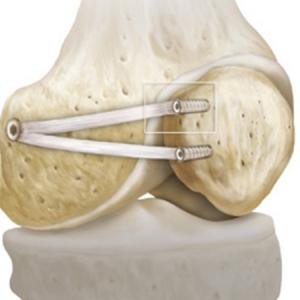

Die Befestigung des in den meisten Fällen abgerissenen Hinterhornes des Meniskus führen wir minimalinvasiv mittels Gelenkspiegelung durch. Hierbei wird die abgerissene Wurzel mit einer speziellen Nahttechnik und einem sehr stabilen Fadenmaterial armiert. Anschliessend wird der Bereich, in dem der Meniskus ausgerissen ist, angefrischt. Mit einem kleinen Bohrer wird nun durch den Unterschenkel ein Kanal gebohrt, durch welchen dann die an der Wurzel befestigten Fäden nach vorne ausgeleitet werden. Hier erfolgt dann unter Zug die Befestigung des Meniskus, exakt an der Stelle des Ausrisses, indem die Fäden vorne am Knochen befestigt werden. Dies kann mit einem kleinen Metallplättchen zusätzlich verstärkt werden.

Nachbehandlung

Bis der Meniskus wieder angeheilt ist vergehen 6 Wochen. In dieser Zeit muss eine Teilbelastung an Stöcken durchgeführt werden. Auch wird die Beugung in dieser Zeit durch eine Schiene limitiert. Schuheinlagen, welche zu einer reduzierten Belastung des Gelenkanteils führen in welchem der Meniskus wieder befestigt wurde kommen nach der Operation ebenfalls zum Einsatz. In wenigen Fällen muss das evtl eingebrachte Metallplättchen wieder entfernt werden.